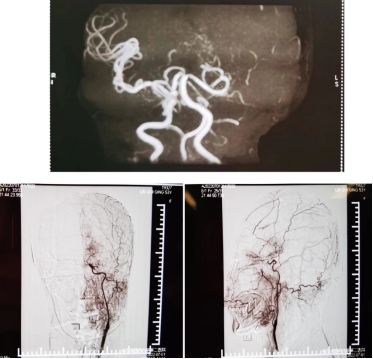

两个月前,刘女士因脑梗死第三次被收治到哈医大二院神经内科病房进行治疗,此时的她已经无法行走、语言笨拙、小便失禁。检查显示,左侧颈内动脉闭塞、右侧大脑前动脉闭塞,60%的脑组织供血差。发生了多次脑梗死,导致脑组织已经千疮百孔。由于药物治疗已经无法控制病情进一步发展,遂邀请神经外科进行会诊。

检查显示左侧颈内动脉和右侧大脑前动脉闭塞

王洪军主任医师介绍,脑组织是不能再生的,坏死后功能就丧失了。患者左侧颈内动脉闭塞,右侧大脑前动脉闭塞,脑血流严重供应不足,极易再度发生脑梗死,尤其大脑前动脉闭塞患者由于代偿极差,脑梗死发生率更高,为保住剩余健康的脑组织,并满足整个左侧脑组织供血,只有对多个位置进行脑血管搭桥手术。